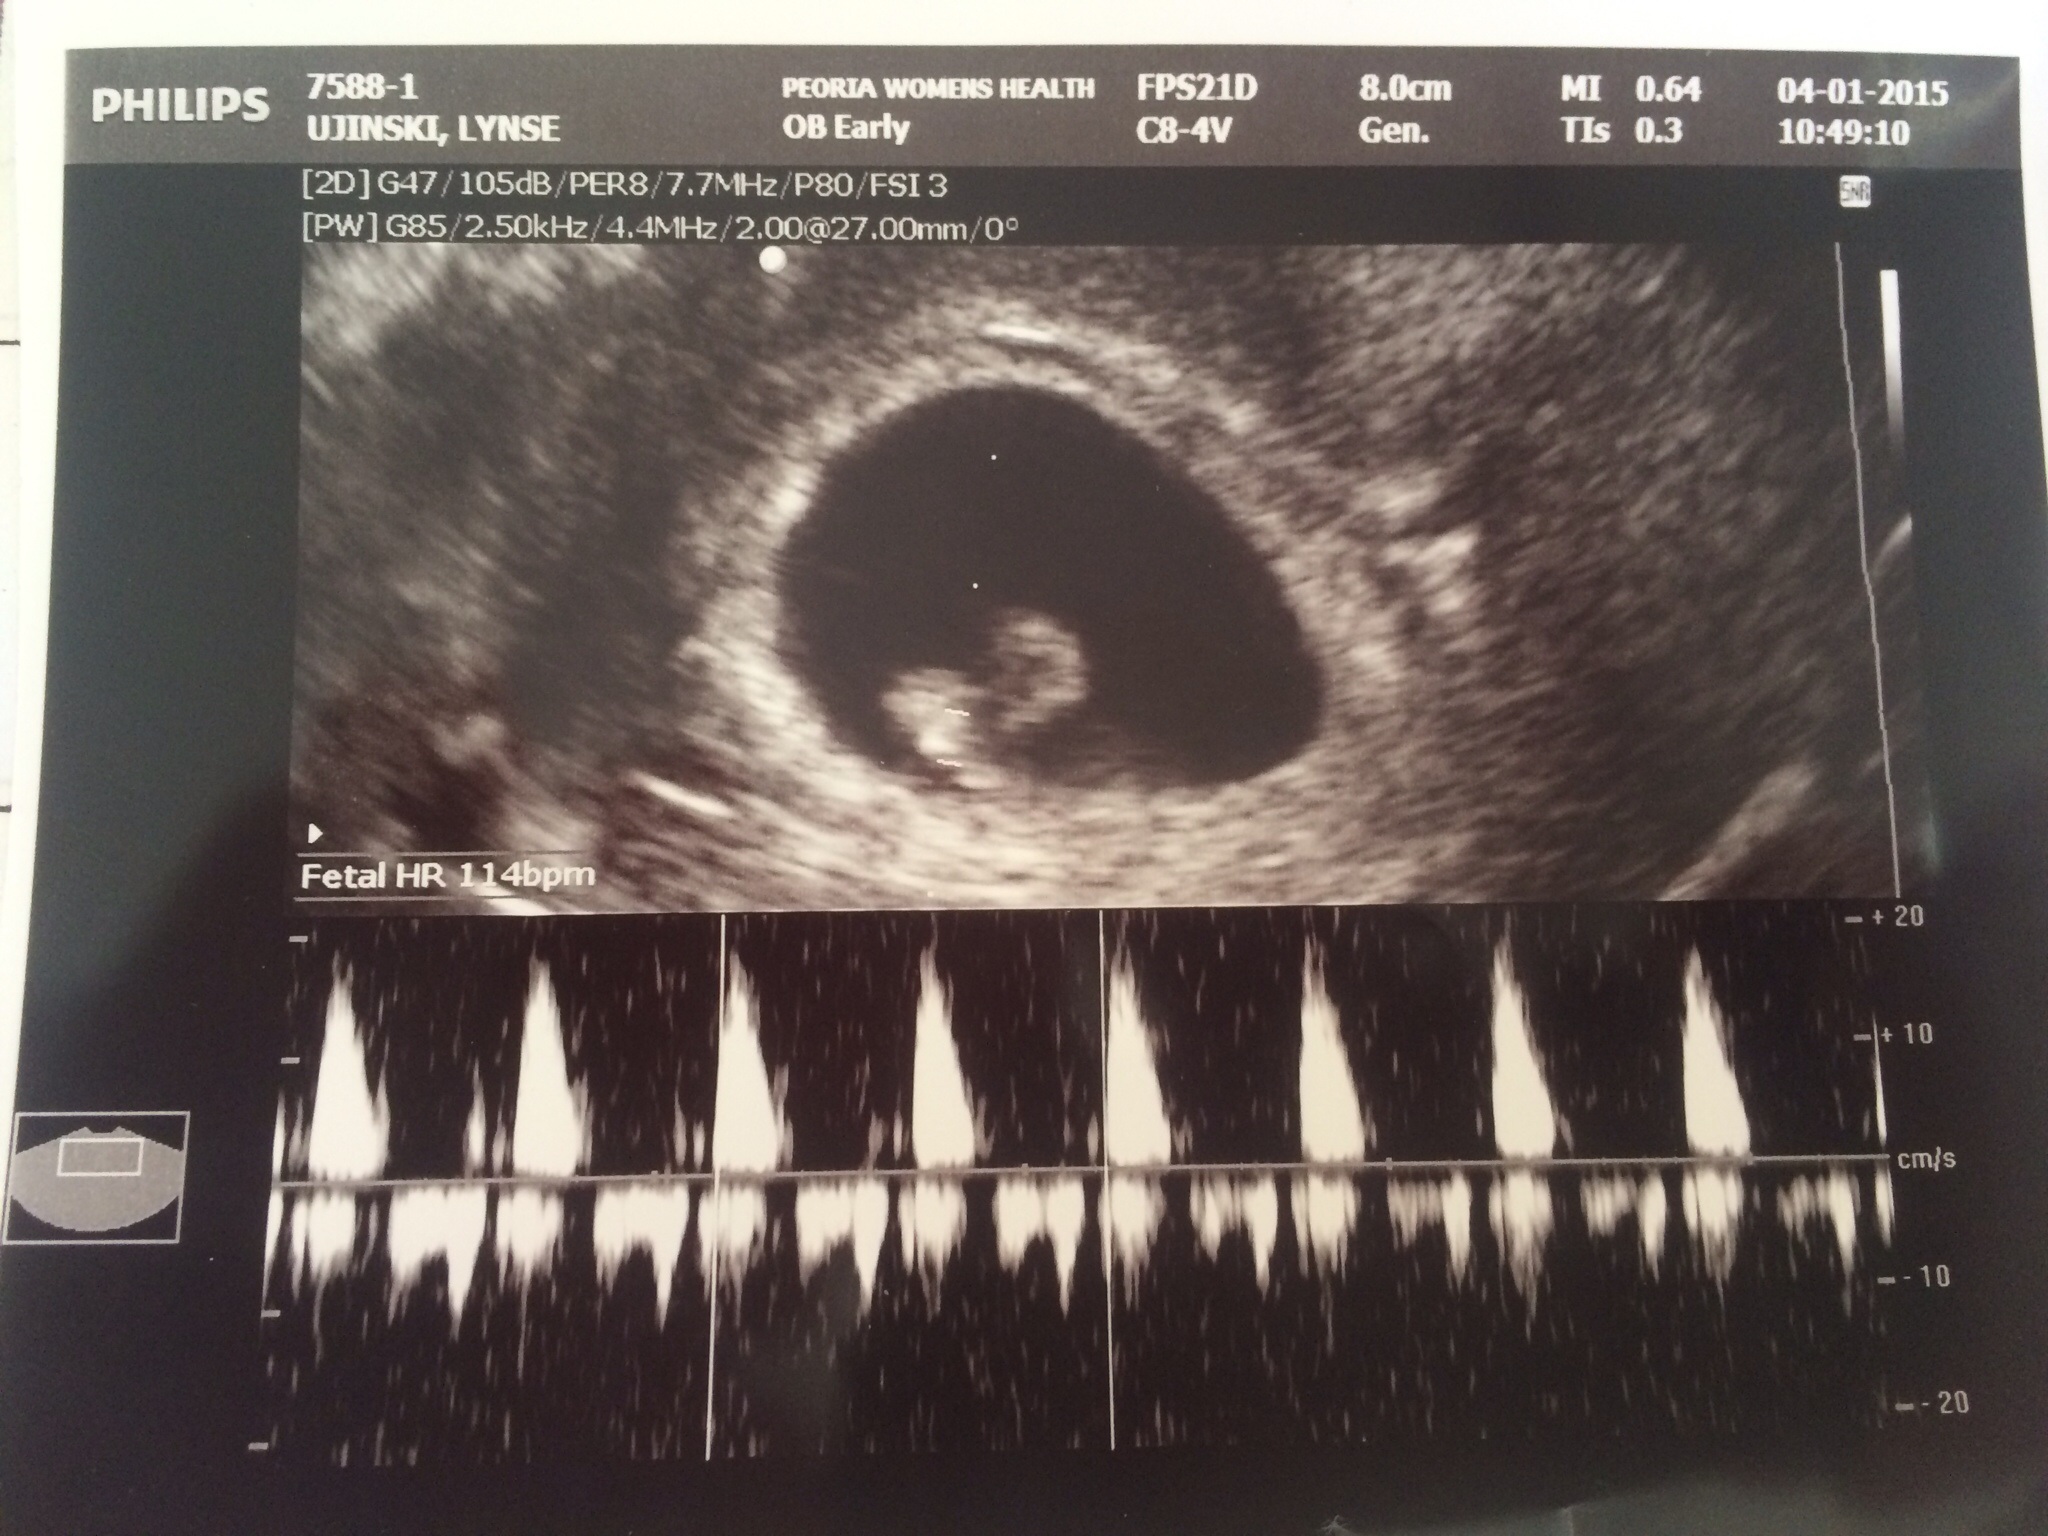

• First pregnancy. Had my first u/s yesterday at 6w 3d....got to see the heart flicker and hear the heartbeat (114)....so excited!!!